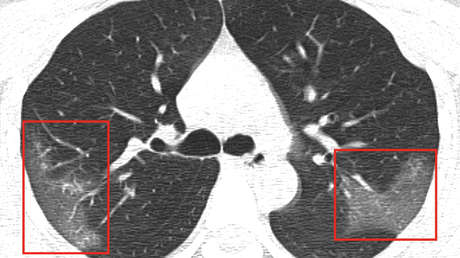

A través de las radiografías, los médicos observaron unas manchas blancas en la esquina inferior de sus pulmones, llamadas por los especialistas como la "opacidad de vidrio esmerilado".

El radiólogo de la Universidad Thomas Jefferson (EE.UU.), Paras Lakhani —que no participó en el estudio, pero examinó las imágenes—, explicó que son habituales en pacientes enfermos de neumonía común y muestran la presencia de líquido en los espacios pulmonares. No obstante, especificó que no son un síntoma claro para diagnosticar el nuevo coronavirus en un paciente, informa Business Insider.

Pero en este caso, los investigadores detectaron que las manchas se extendían hasta los bordes de los pulmones de la mujer, una característica que también se había detectado en los pacientes con SARS y MERS. Lakhani indicó que en las imágenes detectaron que el nuevo brote tiene "muchas características similares" con las otras dos epidemias.

Para descartar que no se tratara de una neumonía, los especialistas repitieron las radiografías al cabo de 3 días, cuando la paciente ya había recibido su tratamiento, y descubrieron que las manchas blancas se habían vuelto más extensas y pronunciadas.